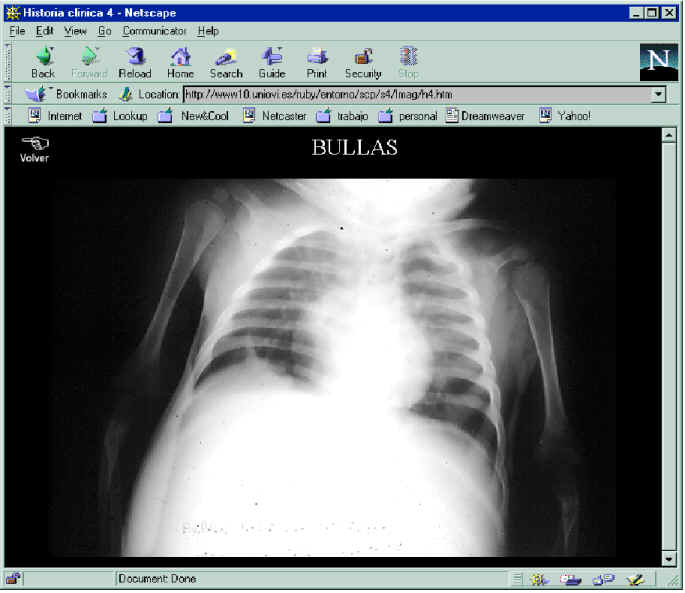

En la figura 7 se puede ver el ejemplo de la historia

clínica de la sesión 4, en la que cita una bulla (figura 8)

detectada al paciente. La figura 9 corresponde a la

presentación anatomopatológica, donde hay una referencia al pulmón que albergaba dicha

bulla (figura 10)